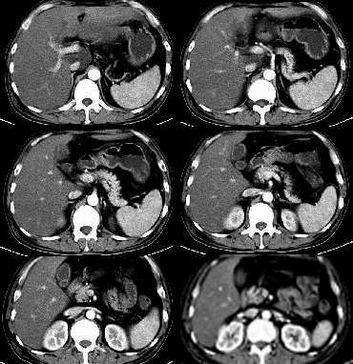

1,肝左叶外恻段似见类圆形稍低均匀密度影,突于肝外,在平扫及动脉期上此可疑病灶更明显。肝内外胆系未见扩张,考虑是外生性肝ca?2,胆囊壁有环壮强化{考虑慢性胆囊炎。}[emb5]

肝左叶外恻段似见类圆形稍低均匀密度影,突于肝外,在平扫及动脉期上此可疑病灶更明显。尾状叶处(膈面下开始出现)呈现更低密度影,边缘不清;ce俩病灶内血管影(门脉左支、下腔静脉)显示的似有受压变形。

考虑:肝左叶占位性病灶(肝ca可能性大),并膈下、肝门淋巴转移。

平扫:肝脏体积增大,密度明显低与脾脏,肝尾叶见一类圆形低密度病灶,并向肝外突出于,大小?边界较模糊,ct值4-10hu(花省伞朋友说的)。肝门增大,似有一肿块。肝内胆管未见扩张,脾不大,密度均匀。

增强:肝尾叶病灶轻度强化(花省伞朋友说的),界限较平扫时清晰,内可见有血管走形,周边血管可见推移,胆囊强化后可见壁较厚,肝门处的肿块似有强化。

意见:1  肝左叶占位,考虑恶性,并肝门部淋巴结肿大。建议mri检查!

1:肝左叶病灶比较明显,似有包膜,动脉期病灶内有不规则片样强化,支持肝癌诊断。2:肝脏增大,密度明显减低,且转氨酶明显升高,应考虑急性肝炎。本人认为:(1)急性肝炎,(2)肝左叶肝癌。